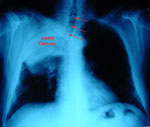

Σχέση μειωμένης πνευμονικής λειτουργίας και καρκίνου των πνευμόνων

Νέα Υόρκη: Καναδοί ερευνητές διαπιστώνουν την ύπαρξη σχέσης μεταξύ της μειωμένης πνευμονικής λειτουργίας και του καρκίνου των πνευμόνων, σύμφωνα με άρθρο που δημοσιεύεται στο επιστημονικό έντυπο Thorax.